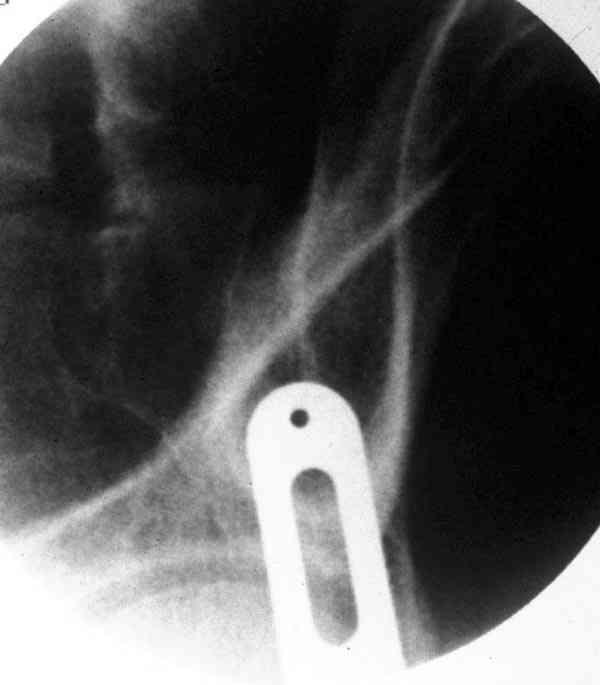

По вертлуге- смог разглядеть только изолированный перелом передней колонны.

Насколько я понял из твоего письма, обращенного к анонимному vit, ты не видишь показаний к реконструкции перелома. Я бы взялся за реконструкцию(илео-ингвинальный доступ), хоть прошел и месяц после травмы: боковая 3Д показывает смещение нагрузочной зоны впадины, что однозначно будет способствовать разрушению хряща головки и впадины( особенно у 16 летнего пациента с ожидаемым высоким уровнем активности) + изменение геометрии впадины за счет неустраненного смещения фрагментов колонны (КТ, 3Д данные).

Сравнивая боковые проекции 3Д реконструкций, разница переломов очевидна: в предыдущем случае на боковой проекции не видно было ступени нагрузочной зоны суставной поверхности - это и объясняет приличную функцию сустава.

По представленным материалам, мне кажется, перелом был передней колонны ацетабулум с минимальным вовлечением нагрузочной поверхности сустава, левосторенний повреждение КПС и лонных костей.

При свежем случае показана фиксация передней колонны к задней (снимки), компрессирующим винтом минимальным перкутанным методом по супраацетабулярной линии и в зависимости от состояния КПС.

iliac view

obturator tear drop view

obturator view

column model